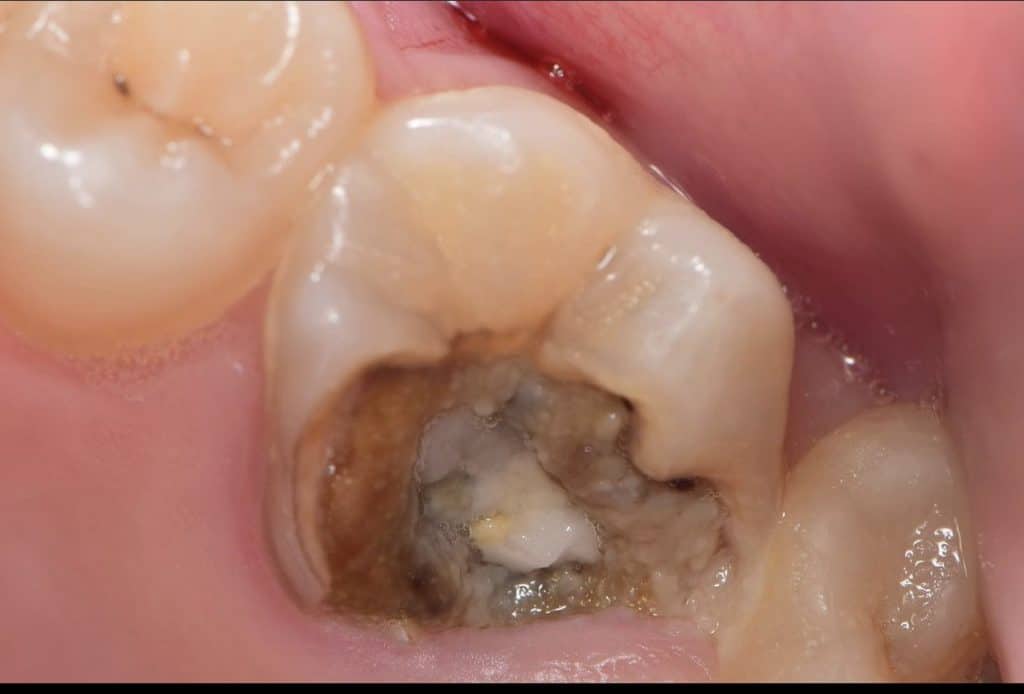

Pre endo build up